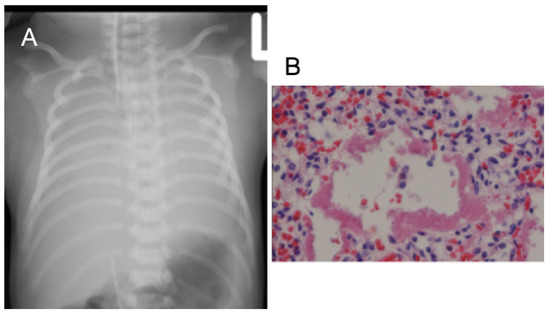

3.5. Case 5